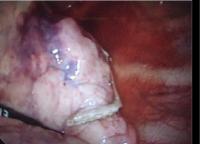

壁側胸膜の腫瘍多発

(白色調結節)

心膜、横隔膜の腫瘍

肺の表面上の腫瘍

術中所見

広背筋による横隔膜再建